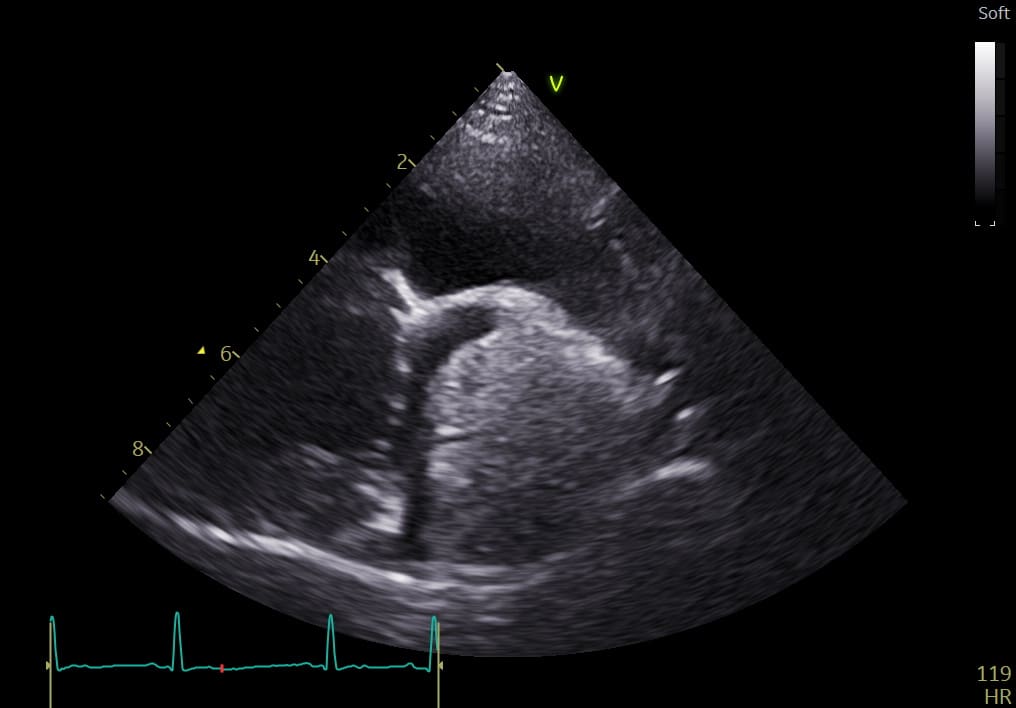

What is the most likely differential diagnosis?

Chemodectoma

Haemangiosarcoma

Myxoma

Leyomyoma